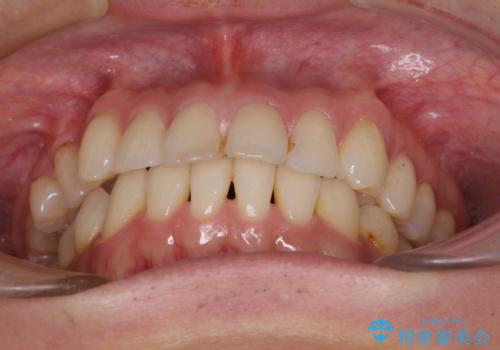

- 治療期間

- 2年8ヶ月

動きにくい歯はやはり動きにくく、咬み合わせ改善に時間を要しましたが、患者様には大変満足していただけました。